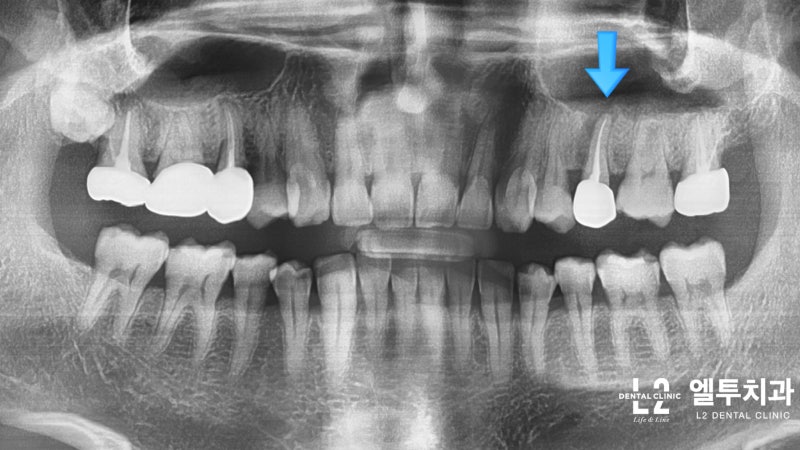

■ 유치의 충치 원인 치료 유치는 영구치로 바뀌기 때문에 부모들은 관리를 하지 않아도 큰 문제가 없다고 생각하는 경우가 많습니다. 하지만 올바른 위치에 치아가 나오지 않는 ‘비정상적 치아 위치’나 상하 메쉬가 어긋나는 ‘비정상 교합’ 등 유치 관리를 소홀히 하면 치아의 비정상적인 배열이 발생할 수 있습니다. 젖니는 미래의 영구 치아를 제자리에 유지하는 데 중요한 역할을 합니다. 위아래 치아가 맞물리지 않는 부정교합은 유치가 충치에 의해 손상되거나 영구치가 공간을 만들기 전에 조기에 빠지면 발생할 수 있습니다. 유치 관리를 소홀히 하면 유치 아래에 있는 튼튼한 영구치를 갖기 어렵기 때문입니다. 충치가 염증을 일으키고 고름이 쌓이게 되면 당연히 밑에 있는 영구치에도 영향을 미치게 됩니다. 초기 충치 모니터링 시에는 여수 슝천동치과병원 바른플랜트에 내원하시어 3개월마다 정기적인 검진을 받으시는 것을 권해드립니다. 치아는 가장 안쪽 신경, 가장 위쪽 상아질 및 가장 바깥쪽 법랑질로 구성됩니다. 충치는 충치가 빠르게 진행되는 질환이므로 처음 나타난 순간부터 잘 관리하는 것이 중요합니다. 문제는 유치의 법랑질과 상아질이 영구치 두께의 절반 정도에 불과하다는 점이다. 충치가 법랑질까지만 확장된 경우 적절한 관리를 통해 충치의 진행을 늦출 수 있습니다. 충치는 빠르게 진행되어 근관 치료가 필요한 지점에 빠르게 도달할 수 있습니다.